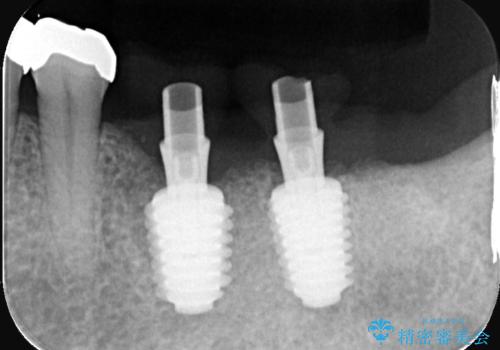

- 治療計画

今回の治療では、まず左下6番と7番の欠損部に、骨の状態を考慮しながら慎重に2本のインプラントを埋入しました。インプラント体と骨がしっかりと結合するのを待った後、最短の期間で最終的な被せ物を装着するための精密な型取りを実施。最終的に、周囲の歯と調和した審美性の高いセラミック製の歯を装着しました。